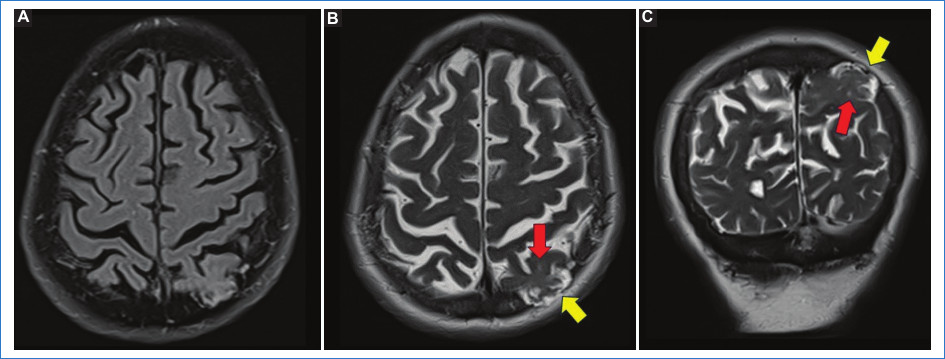

En ocasiones el parénquima cerebral herniado puede mostrar cambios estructurales y de señal en los estudios de RM: atrofia cerebral focal y/o hiperintensidad de señal potenciada en T2 en relación con gliosis, sin restricción en la difusión, ni alteraciones de señal en la secuencia de susceptibilidad magnética (SWI)1.

A continuación, presentamos el caso de un paciente de 75 años que consulta por inestabilidad de dos años de evolución, sin presencia de alteraciones cognitivas, cefalea, náuseas, vómitos ni fiebre. La exploración neurológica y analítica no mostró alteraciones significativas. La TC craneal reveló una lesión lítica de bordes bien definidos de aproximadamente dos cm, que causaba lisis total de la tabla interna y en menor medida de la tabla externa del hueso parietal izquierdo (Fig. 1). Dicha lesión se encontraba ocupada por contenido de densidad intermedia en continuidad con el parénquima cerebral subyacente, siendo sugestivo de herniación encefálica (Fig. 1). Se decidió complementar los estudios con la realización de una RM cerebral y una gammagrafía ósea con 99mTc-metil-difosfonato. En la RM se objetivó la ocupación del área lítica por LCR, meninges y herniación del parénquima cerebral, que en la secuencia potenciada en T2 mostraba pequeñas hiperintensidades de señal secundarias a gliosis (Fig. 2). En la gammagrafía no se identificó depósito patológico de radiofármaco en la lesión parietal izquierda ni a ningún otro nivel óseo. Ante la falta de signos de malignidad de la lesión, se determinó como una GAG con herniación del tejido cerebral. La realización de una punción lumbar descartó la existencia de hipertensión secundaria a una posible obstrucción del drenaje venoso, estableciéndose el diagnóstico de GAG como un hallazgo incidental y sin relación con la clínica de inestabilidad referida por el paciente.